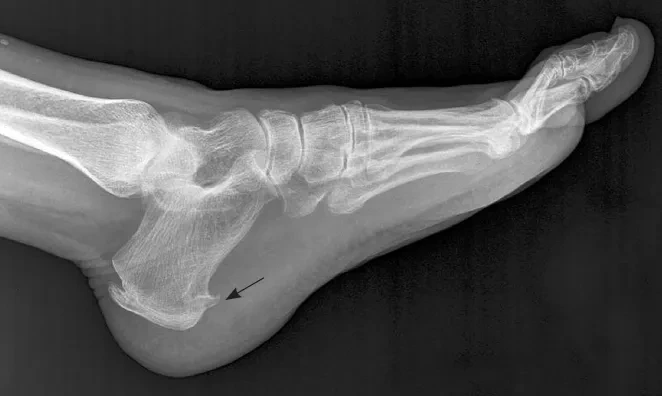

족저근막염은 발바닥의 아치 부분에 있는 '족저근막'이라는 섬유조직이 미세하게 찢어지고 염증이 생기면서 발생합니다. 대부분 아침에 일어나 첫 발을 디딜 때 통증이 극심하죠. 원인은 다양해요. 오래 서 있는 직업, 무리한 운동, 불편한 신발, 또는 발의 구조적 문제 때문일 수도 있어요. 특히 발바닥 충격을 반복적으로 받는 경우, 회복이 느리고 쉽게 재발하는 특징이 있어 치료 기간이 길어지기 쉽답니다.